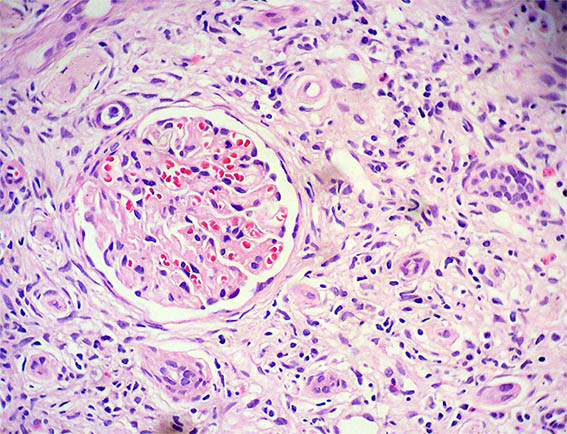

Figure 2. H&E, X200.

Figure 3. H&E, X400. Interstitial infiltrate of lymphocytes, neutrophils, eosinophils, and plasma cells.